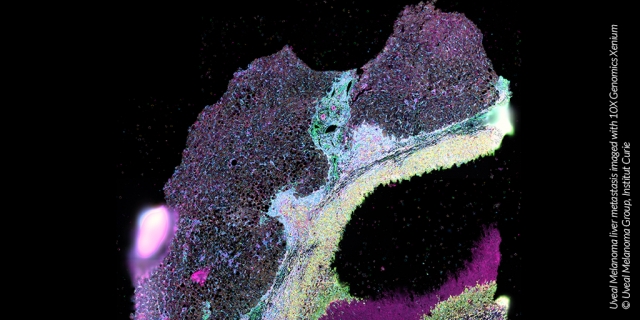

The diversity across tumours from different patients and even across cancer cells from the same patient tremendously complicates the development of treatments. ‘Personalized’ or ‘precision’ medicine aims to overcome this problem by finding a tailored treatment regimen for each patient according to the individual genetic background and tumour molecular profile. This ambitious goal requires proper molecular characterization of patient cancer using high-throughput technologies and advanced imaging technologies. Although cancer multi-scale data are becoming available, these still need to be fully exploited to elucidate the underlying mechanisms and thereby inform patient stratification and treatment.

Since multiple views for the same patients can provide complementary information, multimodal integrative analysis of omics and clinical data has great potential to elucidate the molecular underpinning of cancer types.  Multimodal integration of disease data holds great promise in uncovering intricate relationships among molecular mechanisms collectively contributing to the disease.